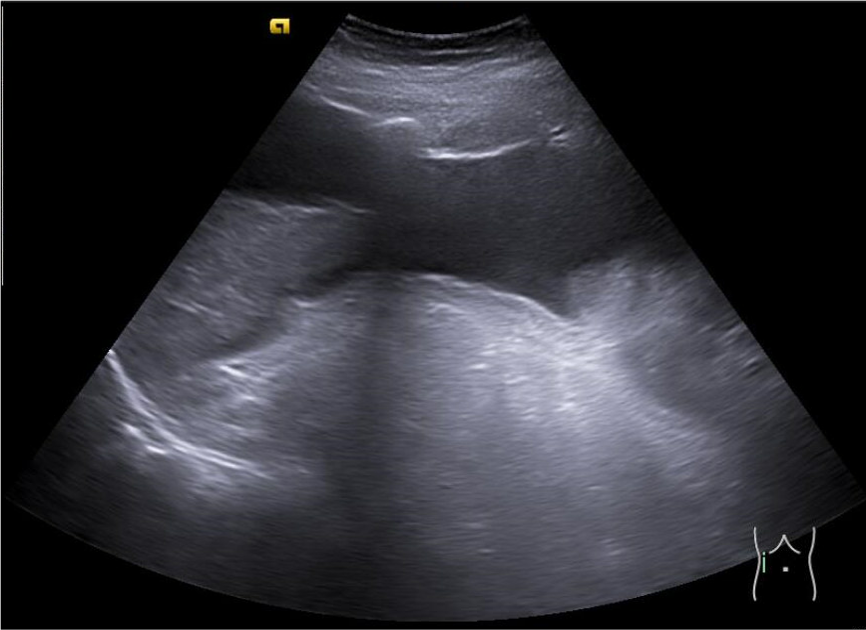

Se realiza ecoPOCUS y se objetiva imágenes anecogénicas en todas las zonas declives, en ambos flancos e hipogastrio y derrame pleural izquierdo.

Una semana después la disnea había remitido, había disminuido el perímetro abdominal y la paciente no presentaba derrame pleural ni ascitis significativa. Se establecieron revisiones en consulta de Atención Primaria cada tres semanas.